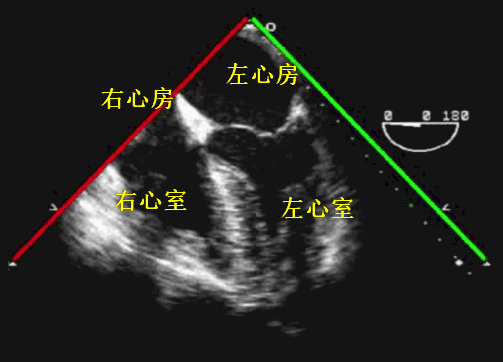

超声探头位于左心房后部(「下刀位置」)、旋转晶片角度约 0~10°(「切割方向」)、显示 4 个腔室;通过轻微后屈探头、尽可能多显示左室心尖部。图像中包括左心房、部分右心房、二三尖瓣以及左右心室等结构。

该如何理解掌握此切面的构成?图像切面始于左心房,从后前位可见 0~10° 的晶片角度相当于身体的水平切面;因此切面会经过二尖瓣中心、止于左心室心尖部(图 7)。通常能看到二尖瓣前叶(AMVL)及后叶(PMVL),其中二尖瓣前叶更为居中。

结合动图 8,便可更好理解该切面的构成。此切面主要用于诊断二三尖瓣疾病、房间隔缺损及判断心腔大小、心室功能等。